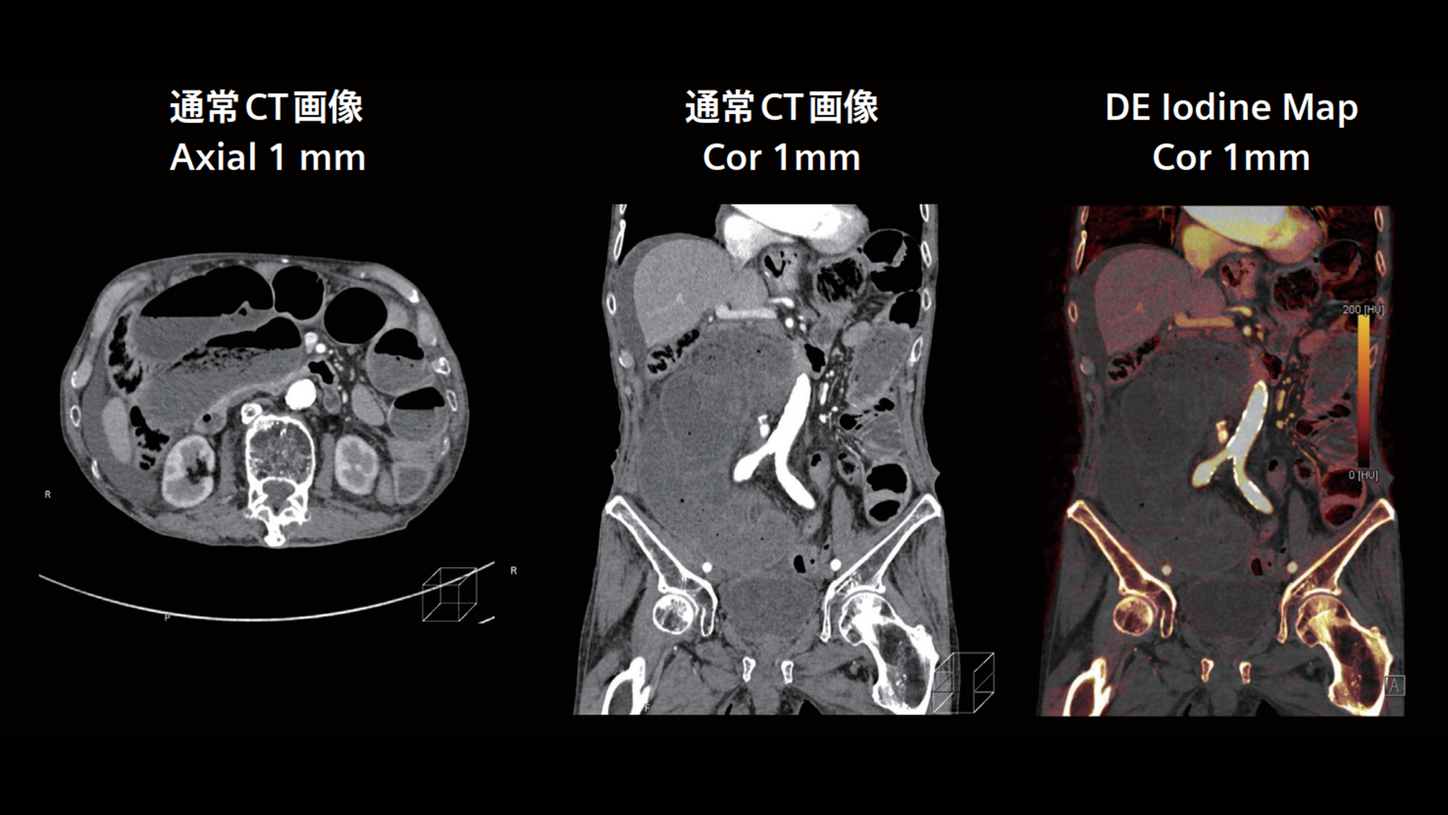

DE Iodine Map ~ 絞扼性イレウスによる虚血評価

イレウス症例では、外科手術のため患者を他院へ転送する必要があるため、Dual Energyによるヨードマップの活用は診断確信度の向上に繋がり、非常に有用です。SOMATOM Pro.PulseはDE 撮影に制約がなく、後処理の負担もありません。その上で、読影医にとって診断に必要な判断材料が増えることで、より正確な診断が可能となります。本症例では、Iodine Map により右下部小腸の血流不良が明瞭に描出され、迅速かつ的確な判断に寄与しました。

放射線科 渡邉 順久 部長